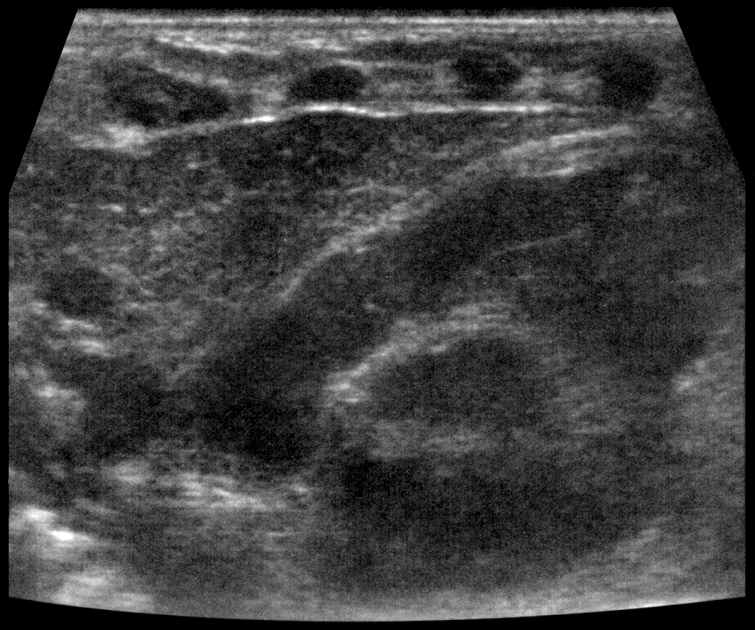

УЗИ диагностика кольцевидной поджелудочной железы: что важно знать